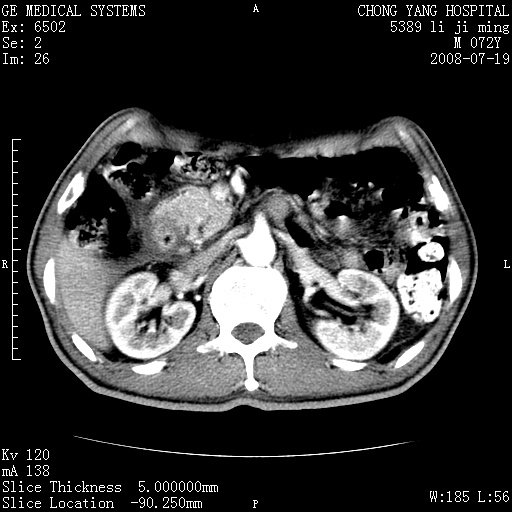

以下是引用zjzjr在2008-7-19 20:57:00的发言:[br]胰头增大,边缘模糊,周围可见渗出影,右侧肾前筋膜增厚.支持胰腺炎.

以下是引用yangyudong333在2008-7-20 6:56:00的发言:[br]胰腺增大尤以胰头明显,边缘模糊,周围可见渗出影,右侧肾前筋膜增厚,肠管於涨.支持胰腺炎

以下是引用不学无术在2008-7-19 23:15:00的发言:[br]胰腺增大尤以胰头明显,边缘模糊,周围可见渗出影,右侧肾前筋膜增厚,肠管於涨.支持胰腺炎